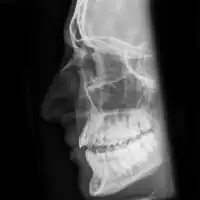

| Plain X-ray showing a nasal fracture | |

The most common causes include assault, trauma during sports, falls, and motor vehicle collisions.[1] Diagnosis is typically based on the signs and symptoms; with plain X-ray rarely of benefit.[1][6] CT scan may be useful if concerns of other fractures or complications are present.[6][4]

Nasal fractures are usually identified visually and through physical examination.[1] Medical imaging is generally not recommended.[1][2] A priority is to distinguish simple fractures limited to the nasal bones (Type 1) from fractures that also involve other facial bones and/or the nasal septum (Types 2 and 3). In simple Type 1 fractures X-Rays supply surprisingly little information beyond clinical examination. However, diagnosis may be confirmed with X-rays or CT scans, and these are required if other facial injuries are suspected.[2]